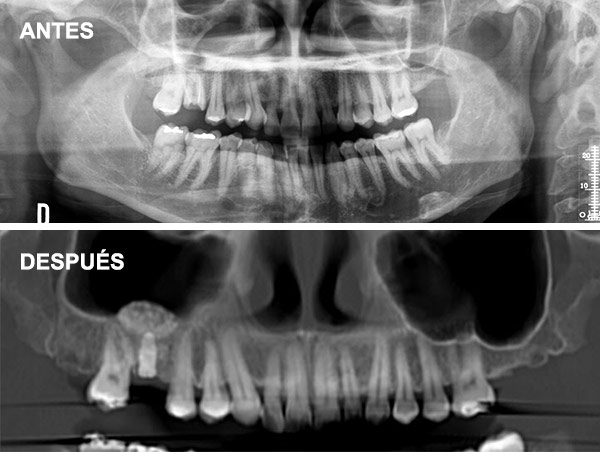

Esta técnica consiste en aumentar la altura y anchura del hueso en los maxilares introduciéndonos en el seno para conseguir una base ósea que permita la colocación de implantes.

Cuando no hay hueso ni distancia suficiente entre el maxilar superior y el seno (altura menor a 5 mm) que imposibilita la colocación de implantes.

Se coloca una membrana y un injerto de hueso liofilizado, un compuesto de procedencia bovina que actúa como osteoinductor (Bio-Oss), así una vez colocado induce al hueso a formar nuevas células. Lo que se intenta hoy en día es encontrar una buena calidad de injerto para acortar el período de formación de hueso. También se coloca una membrana sobre este injerto.

¿Qué es la Elevación Atraumática?

Se realiza a través de la misma osteotomía de colocación del implante, utilizando fresas o dispositivos especiales para levantar la membrana sinusal de manera indirecta.

Indicaciones: Se recomienda cuando existe una altura de hueso residual moderada (alrededor de 5-8 mm) y el aumento necesario no es muy grande.

Es menos invasiva, con una recuperación más rápida y menor riesgo de complicaciones y molestias postoperatorias.